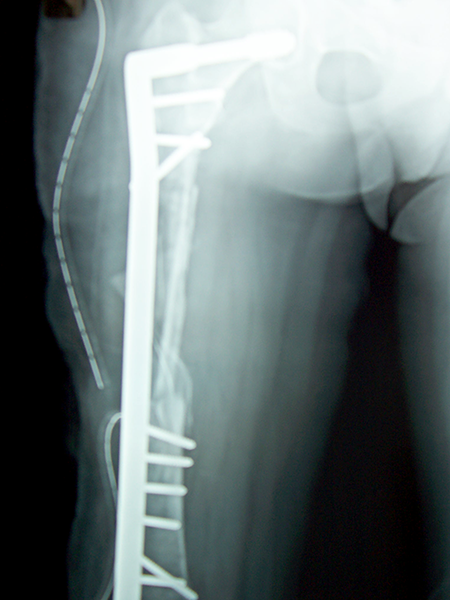

Case:5 Ewing sarcoma with implant failure

Breakage of Nail

Refixation with Angle Bladed Plate and Sever Graft

Ewing's Post Nailing and Bone Grafting

3 Months Post -Op

6 Months Post-Op